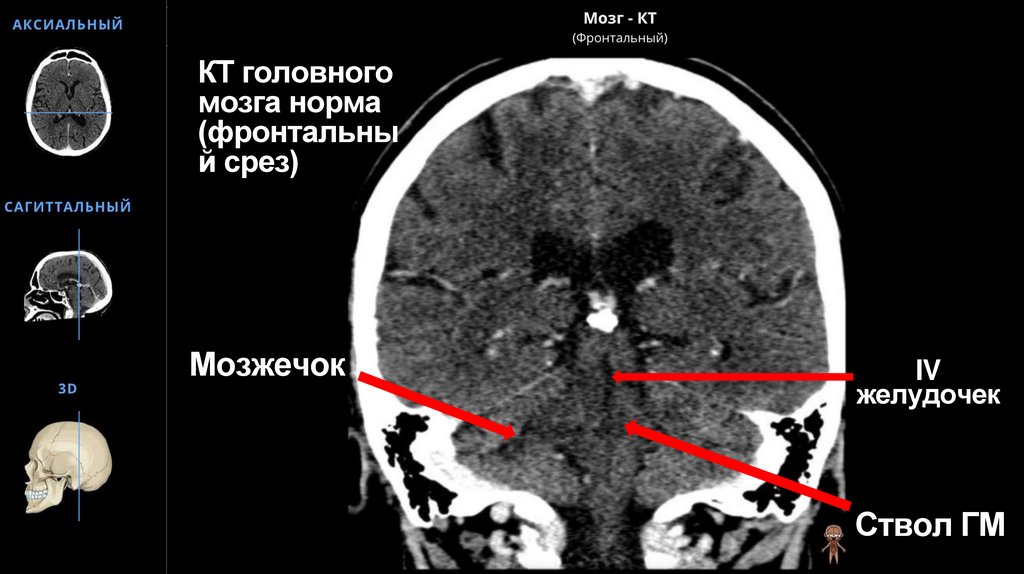

КТ головного мозга норма (фронтальный срез)

60. КТ головного мозга норма (фронтальный срез)

КТ головного

мозга норма

(фронтальны

й срез)

Мозжечок

IV

желудочек

Ствол ГМ